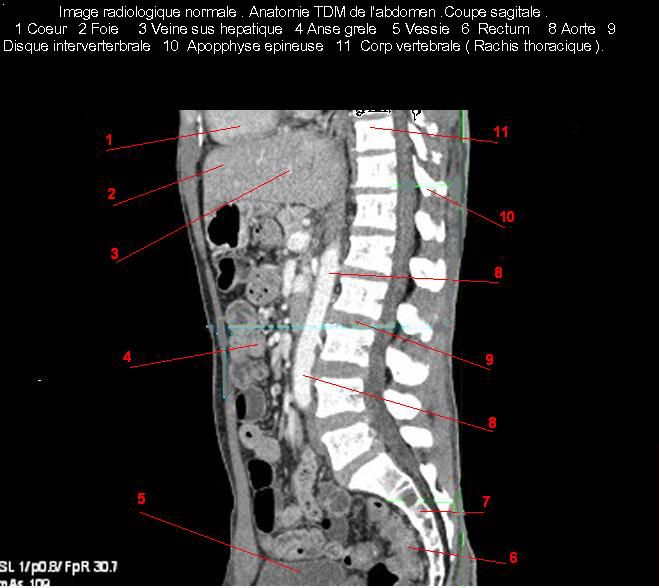

Images radiologique TDM normale de l'abdomen et tube digestif en coupe sagitale ( CT scanner )  :

Coupe axiale     Coupe frontale      Coupe  sagitale